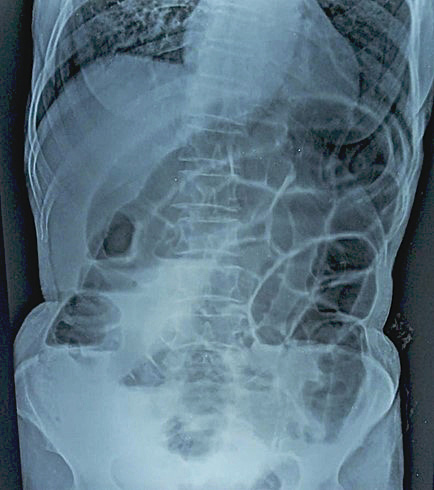

Routine laboratory investigations were unremarkable except for ABG which was suggestive of metabolic acidosis. Erect Abdominal X-ray showed multiple air-fluid levels with dilated bowel loops and absence of rectal gas shadow, indicative of mechanical obstruction (Figure 1).

Figure 1. Erect Abdominal X-ray showed multiple air-fluid levels with dilated bowel loops